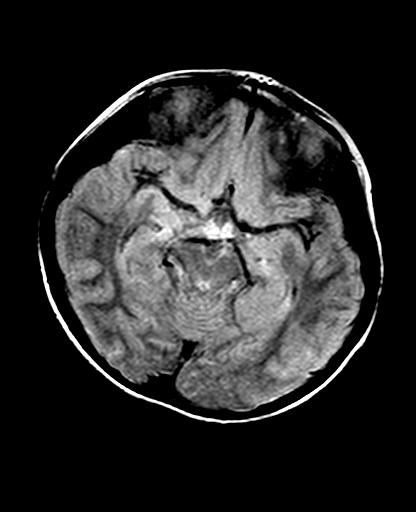

标题: PED2848:脑内病变2

头痛10天、间断呕吐2天。f 6岁

入科化验血清铜及铜兰蛋白均减低,脑脊液正常,血清神经原烯醇化酶明显增高。wbc:5.94x109/l、

临床表现及实验室检查符合肝豆状核变性

符合肝豆状核变性。

肝豆状核变性可能性大。